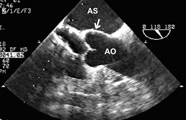

Ecografia (=ultrasonografia) este o metoda de diagnostic de mare utilitate in toate bolile care afecteaza organe in care in mod obisnuit nu se afla aer (exemple: ficat, rinichi, splina, vezica urinara, ovare, prostata, inima etc).

- ecografie abdominala